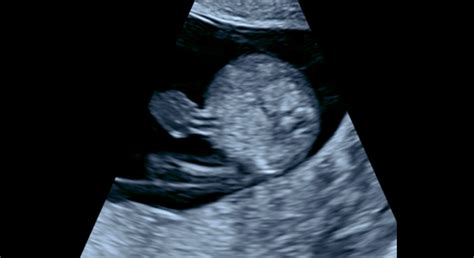

Základným ultrazvukovým vyšetrením v tehotenstve je ultrazvuk v 1. trimestri. Prebieha približne v 6. až 12. týždni tehotenstva. Stanovenie dĺžky tehotenstva je veľmi dôležité najmä u žien s nepravidelným menštruačným cyklom, aby lekár správne stanovil očakávaný dátum pôrodu. Ideálne je absolvovať toto meranie v 8. až 9. týždni. Potvrdenie životaschopnosti plodu - srdiečko vidno pulzovať od 6. až 7. týždňa. Cieľom prvého ultrazvuku v tehotenstve je potvrdiť, že sa embryo nachádza v maternici a nejde tak napríklad o mimomaternicové tehotenstvo, potvrdiť, že dieťatku bije srdiečko, určiť počet plodov a zhodnotiť stav maternice, vaječníkov a malej panvy.

Samotné ultrazvukové vyšetrenie medzi 11+0 a 13+6 týždňom gravidity poskytuje množstvo informácií. V tomto období sa dajú pozorovať niektoré znaky (markery), ktoré môžu signalizovať závažné chromozomálne abnormality plodu. V prvom trimestri sme schopný detekovať až 75% abnormalít plodu. Počas prvého ultrazvukového vyšetrenia je možné počuť tlkot srdca plodu a určiť jeho srdcovú frekvenciu. Počas vyšetrenia je možné určiť riziko nedonosenia plodu a riziká abnormalít embrya. Spočiatku je vhodnejší transvaginálny ultrazvuk, čiže ultrazvuková sonda je zavedená do pošvy. Neskôr lekár prejde na transabdominálny ultrazvuk, keď pozerá dieťatko cez brušnú stenu. Aj v neskorších štádiách tehotenstva však môže siahnuť ešte po transvaginálnom ultrazvuku, napríklad pri zisťovaní dĺžky krčka maternice.

Prvý ultrazvuk v tehotenstve sa vykonáva v 11. - 14. týždni. Vyšetrenie v prvom trimestri zobrazuje: termín počatia; štruktúru a tonus maternice; miesto uchytenia placenty; počet embryí; veľkosť plodu. Počas prvého ultrazvukového vyšetrenia je možné počuť tlkot srdca plodu a určiť jeho srdcovú frekvenciu. Počas vyšetrenia je možné určiť riziko nedonosenia plodu a riziká abnormalít embrya. Medzi hlavné body, na ktoré sa lekár počas tohto vyšetrenia sústreďuje, patrí v prvom rade potvrdenie početnosti tehotenstva, a teda koľko plodov sa v maternici uchytilo. Plod sa v rámci prvého ultrazvuku v tehotenstve zvykne merať za pomoci samotného ultrazvukového prístroja, pričom výsledky tohto merania môžu vo veľkej miere potvrdiť prítomnosť takmer 50 percent vrodených chýb a chorôb.